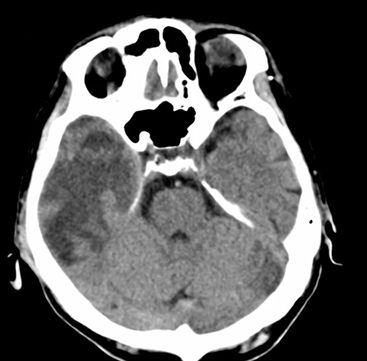

神経所見が認められるため頭部CT撮影。

CTではLDAと周囲の強い浮腫性変化。

左は脳溝がみられるが、右では消失している。

転移性脳腫瘍疑い。